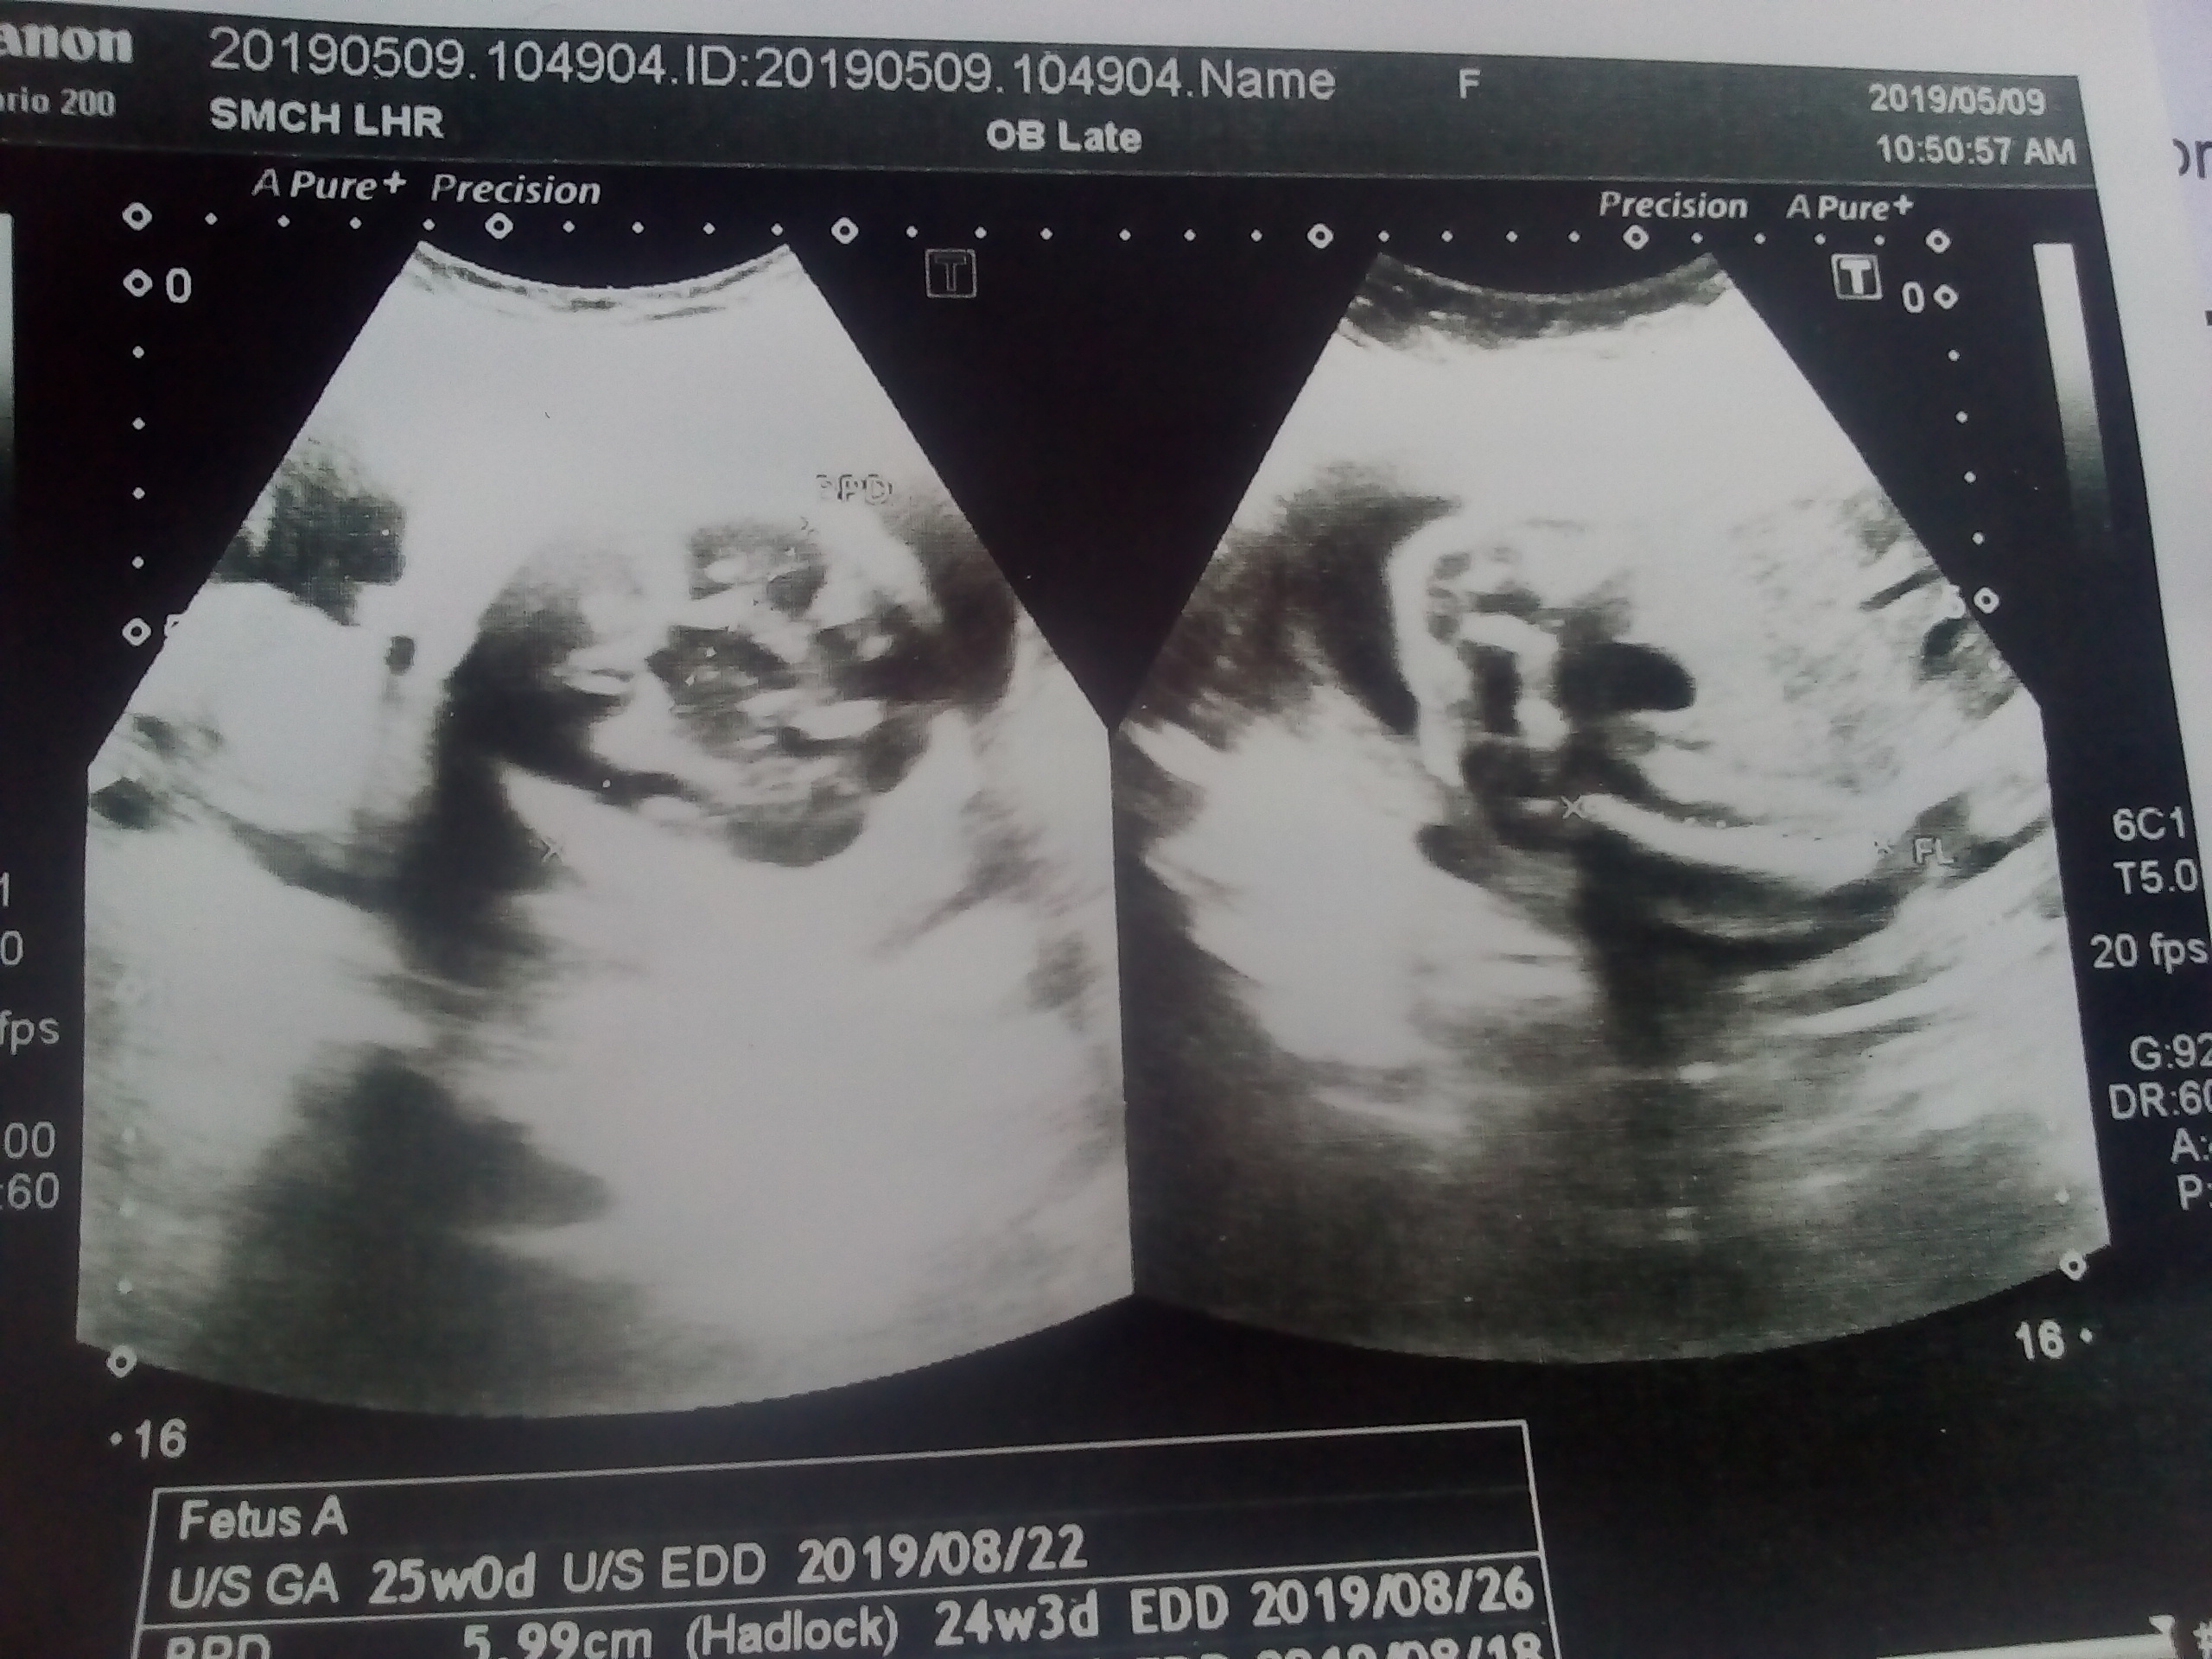

aslam o alikum, meri 25 weeks pregnancy ki altrasound pics Gender bta sakty hen altra sound pics dekh k please....... jazakAllah

Thank you for your mail. it is not possible on pics to tell you the gender.. This requires real time imaging.

Ws.. Unfortunately its not possible to comment about gender on still/static images. You can ask your radiologist while he/she is performing the ultrasound for your gender related queries. I hope that helps :)

Not possible with the provided images ?